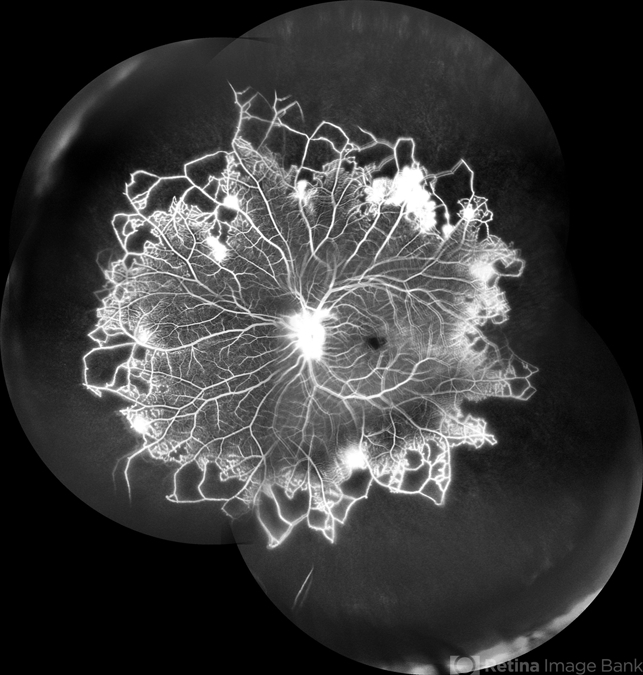

- CNP areas, takayasu arteritis

- A case of 16 year-old female with combined RD in RE. Fundus examination & FFA revealed 360 degrees non-perfusion in periphery in non-symptomatic eye.